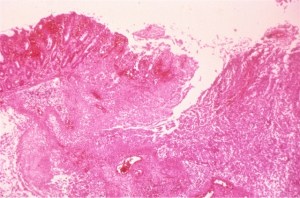

Klebsiella and Raoultella both are gram negative bacilli that form lactose fermenting, yellow, mucoid bacterial colonies. The bacterial colonies appear mucoid because of the bacteria’s polysaccharide capsule. Distinguishing these two types of bacteria requires molecular analysis as their morphology can be identical. In our initial identification process, only one type of bacteria was detected on the urine culture. Given the gram stain and colony morphology, our differential included Klebsiella, Enterobacter, and Roaultella. The bacteria was verified as Roaultella species using mass spectrometry. However, our laboratory also received two sets of blood cultures which showed the same morphology as above but the bacteria was identified as K. oxytoca. This prompted a review of the urine culture in which a subtle second bacterial colony morphology was seen and confirmed as K. oxytoca.

In summary, our patient had a urinary tract infection caused by Roaultella and Klebsiella which was the source of the patient’s sepsis. Only the Klebsiella was detected in his blood stream. Raoultella and Klebsiella are both gram negative, oxidase negative, non-motile, capsulated, facultative anaerobic bacilli within the Enterobacteriaceae family. Raoultella was initially classified within the Klebsiella genus, but reclassified based on comparative analysis of the 16S rRNA gene and rpoB gene which encodes the β subunit of bacterial RNA polymerase. Members of the Raoultella genus include R. electrica, R. terrigena, R. planticola, and R. ornithinolytica and are found in the environment, specifically in plants, soil, and water. Raoultella species are rare in human disease but have been documented to cause bacteremia, urinary tract infection, conjunctivitis and cholecystitis.